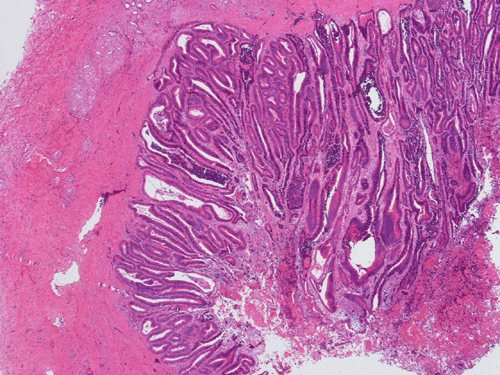

Pathology of the Case: At low magnification, a few small nodules (arrow in Panel A) can be seen with the hematoxylin and eosin stained section. On medium magnification, these nodules correspond to sharply defined granuloma without necrosis. These granuloma are not associated with a high density of lymphocytes in the surrounding liver parenchyma (Panel B and C). Multinucleated giant cells (arrow in Panel C, magnified in Panel D). On reticulin stain, there are reticulin fibers that extends into the granuloma (Panel E). Trichrome stain demonstrated bridging fibrosis (Panel F). The granuloma are well defined and some of them are surrounded by fibrous tissue (Panel G). Immunohistochemistry demonstrated preservation of bile ductules as well as proliferation of ductules (Panle H). No residual ductules are noted in the granuloma as revealed by immunohistochemistry for CK7 (Panel I). Neither acid fast bacilli or fungal organisms are identified by acid fast stain and Gomori's methenamine silver (GMS) stain.

Histopathologic features of sarcoidosis include scattered granulomas in the liver, which may tend to be portal or periportal. Multinucleated giant cells, epithelioid cells, and a variable but usually minimal inflammatory cellular response is present. The granulomas, like in sarcoidosis occuring in other organ systems, tend to be well-demarcated or "clear cut", several granulomas are often comparable in size, and necrosis is not typically present. Asteroid bodies, intracellular vacuolated structures resembling a sea anemone, may be found within the giant cells. Large basophilic, round to roughly oval, and concentrically laminated, Schaumann bodies may be evident in the sarcoid granuloma. None of these inclusions are pathognomonic feature of sarcoidosis, however, do suggest this diagnosis. Ductopenia, cholestasis and features of chronic cholestasis resembling PBC have been described in the cases of sarcoidosis. Severe fibrosis and cirrhosis in conjunction with portal hypertension may be present in sarcoidosis. End stage liver disease in sarcoidosis has been successfully treated by orthotopic liver transplant and recurrent disease has been reported in one such case. Reticulin fibers has a tendency to extend into the granulomas as illustrated in this case.